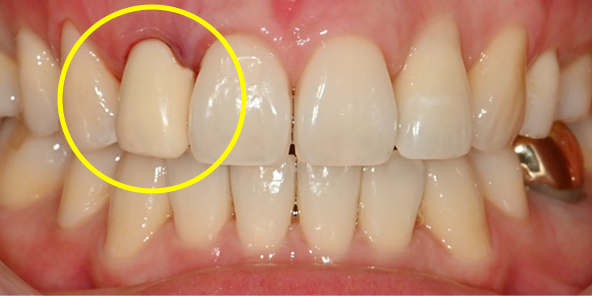

내원 당일 이루어지는 임플란트 기술력! 하루 완성 임플란트는 당일에 식립하고

임시 보철물까지 완성됩니다.

일상생활이 가능하도록 임시 보철물 완성

압도적인 시간 단축,

하루 완성 임플란트